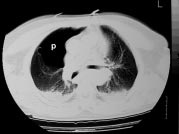

Figure 6: Intérêt de la tomodensitométrie dans le bilan lésionnel des traumatismes du thorax.

A. Pneumothorax antérieur limité (p).